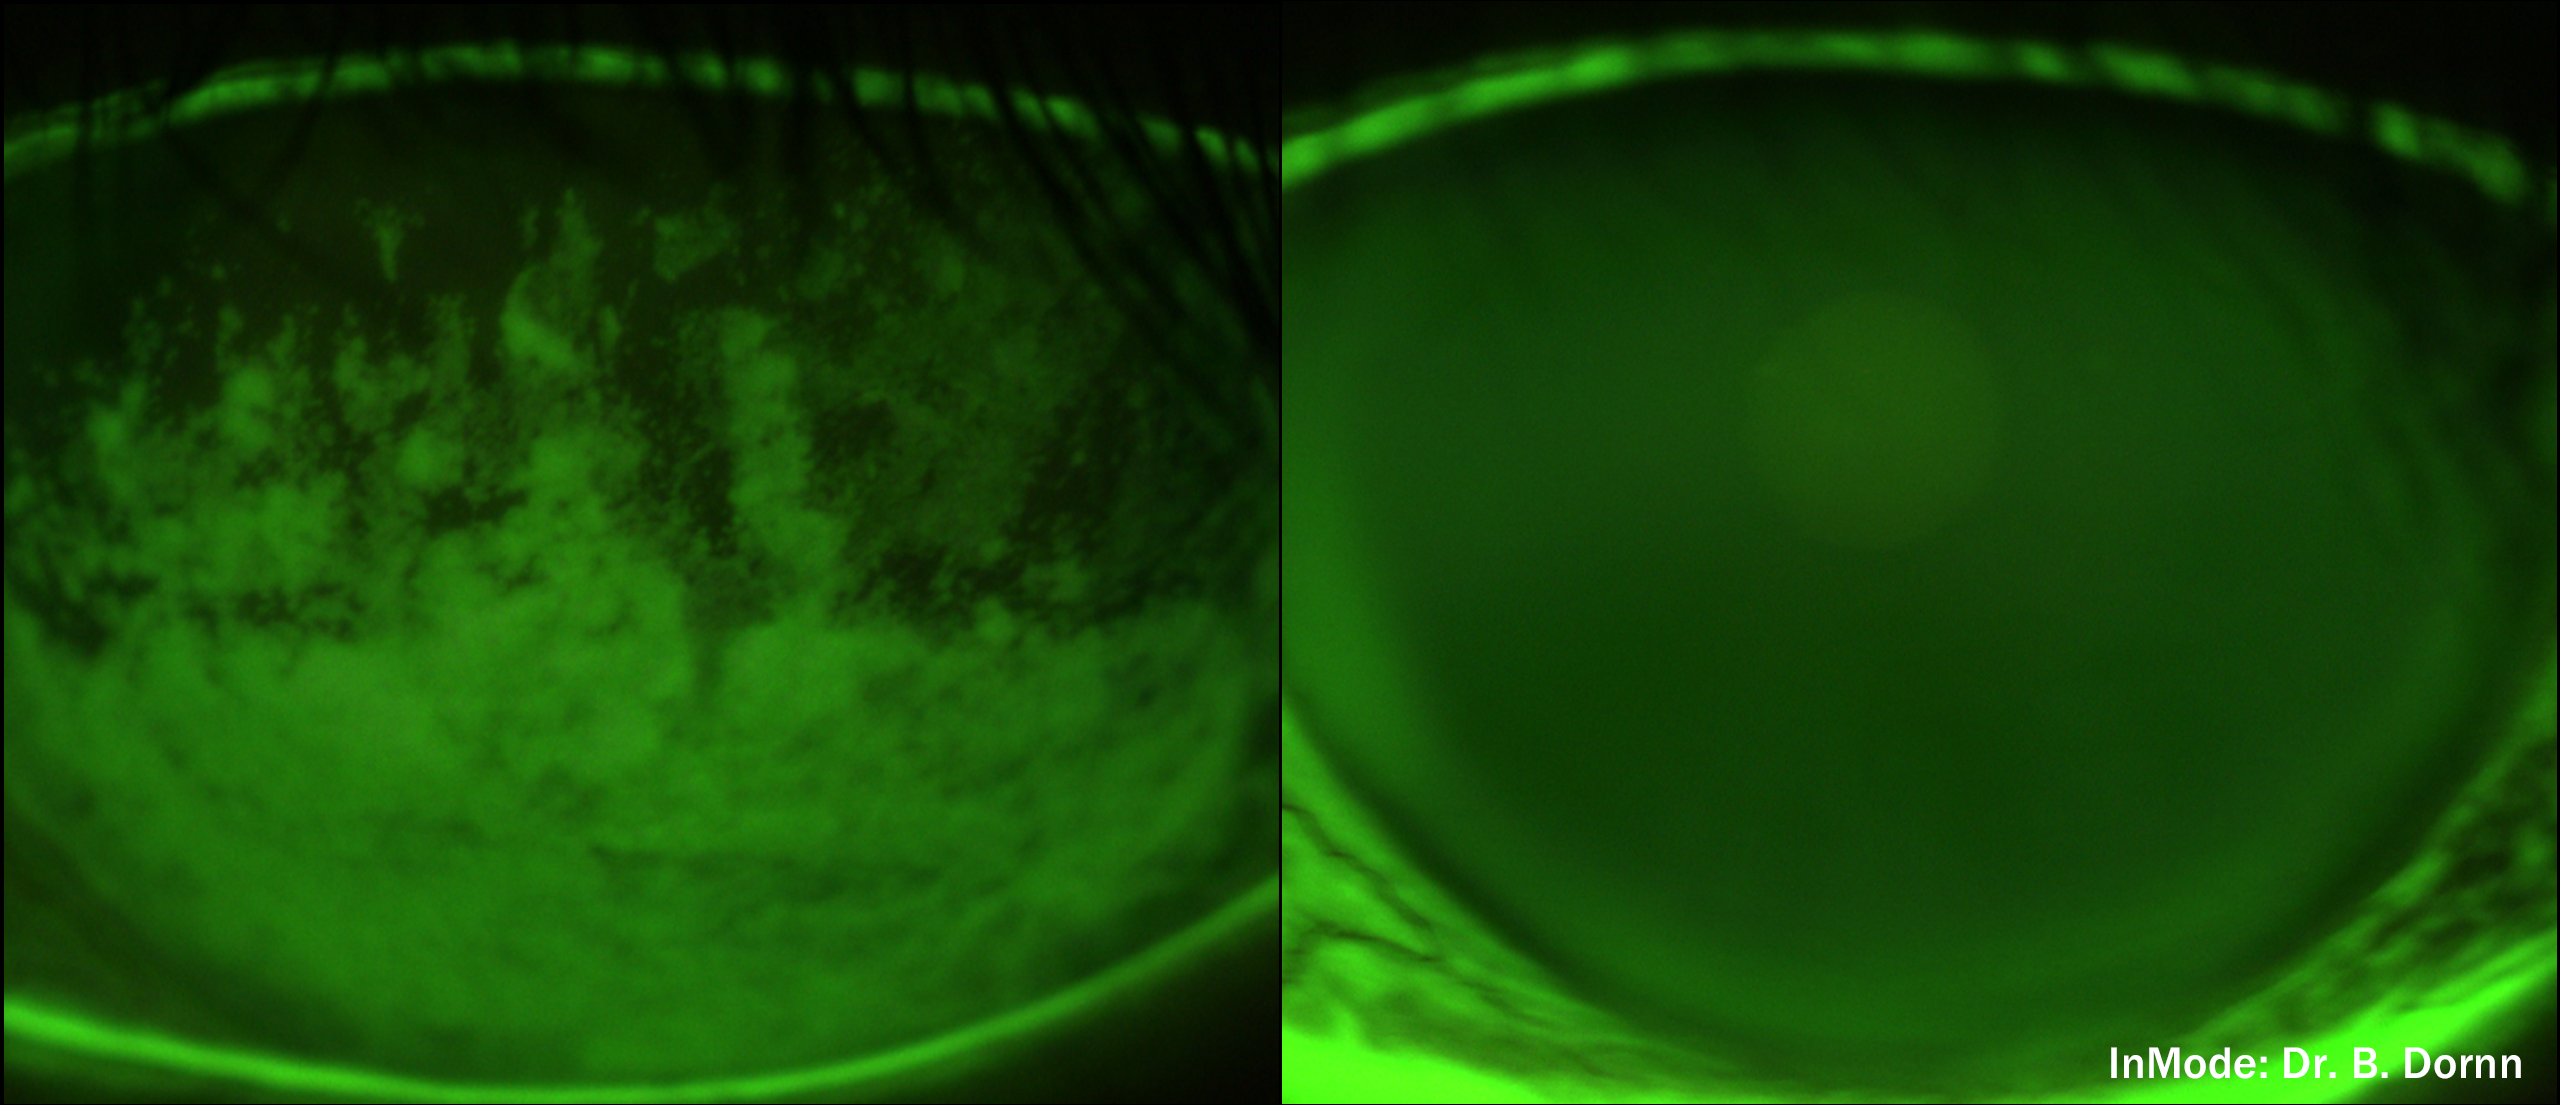

See the Difference: Before & After Photos